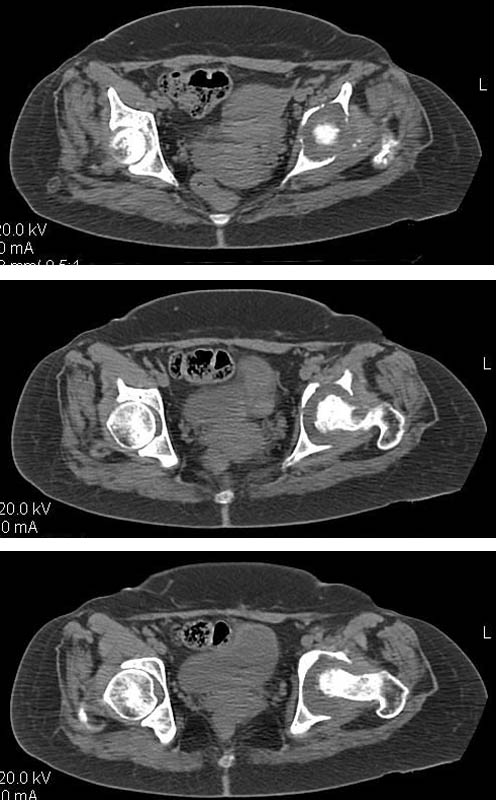

Женщина, 45 лет. В марте перенесла левосторонний коксит неизвестной этиологии. Специфику и онкологию исключили.

Дополнение - проконсультировался с женой-она специалист рентгенолог - на КТ большое колиество мягкотканного компонента - ищите микоплазмы или бруцеллу. Я склоняюсь к виопсии.

Пртезирование через пол года после коксита закончившегося лизисом сустава, который на снимках выглядит как гнойный? Что значит неизвестной этиологии?

Если Вы в состоянии выполнить КТ и умеете ставить протезы, то почему бы не установить этиологию. Делать протезирование после коксита, не выяснив его причины, это порочная медицина.